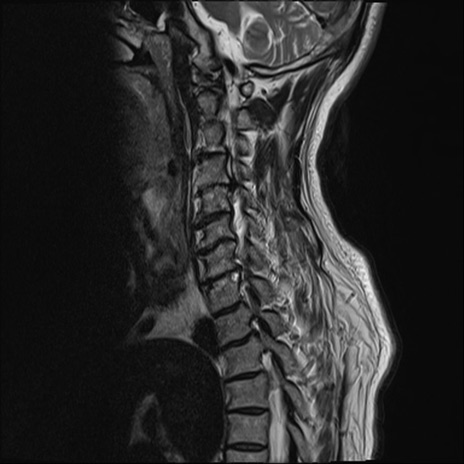

【整形】TIPS症例7 頚椎MRI T2WI(矢状断像)

頚椎MRI

T1WI(矢状断像)